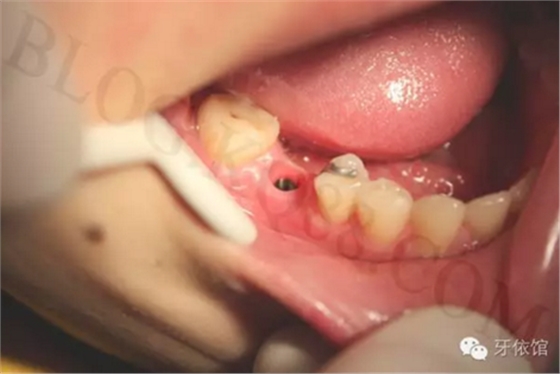

安裝印模帽(開放式)。

連接印模帽后拍x光片,檢查印模帽與種植體之間是否緊密相連。